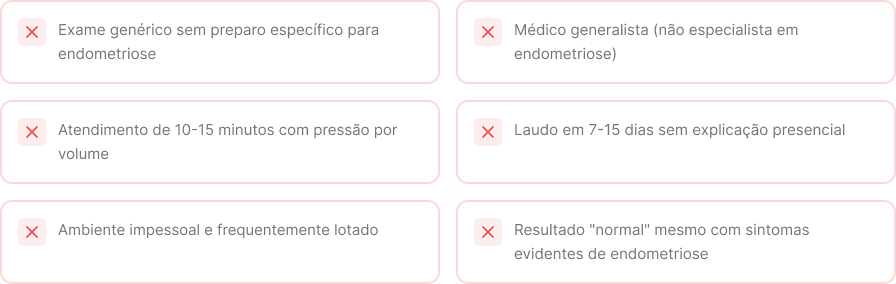

Compare: o que você encontra em outros lugares vs. o que recebe no Instituto Pure

Enquanto isso, nos convênios você tipicamente encontra:

Convênios realizam ultrassonografias de rotina, sem preparo intestinal e, em geral, com médicos generalistas em atendimentos rápidos. Por isso, muitos resultados vêm “normais” mesmo em mulheres com sintomas evidentes. Aqui, o exame segue um protocolo especializado, com preparo intestinal e é realizado por um médico dedicado exclusivamente à endometriose.